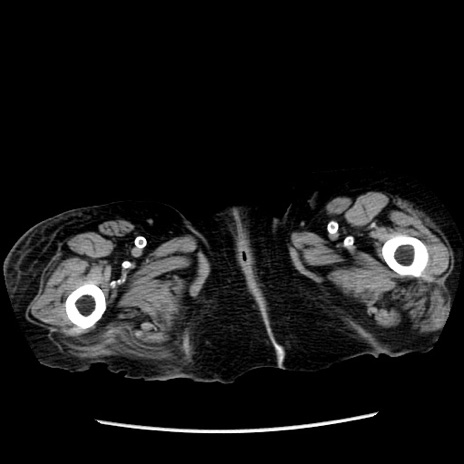

症例14(横断像)

【症例】 90歳代女性

【主訴】 腹痛・嘔吐

【現病歴】今朝から左側腹部痛を認めた。 経過観察していたが、嘔吐を認めたため来院。

【既往歴】 子宮癌術後

【身体所見】 意識清明、BP 127/54mmHg、P 98bpm Sp02 95%(RA)、BT 35.8°C、腹部平坦・軟腸ぜん動音聴取良好、右下腹部圧痛(+) 反跳痛なし

【データ】WBC 9800、CRP 0.46